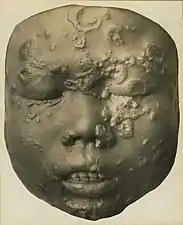

Rhinopharyngitis mutilans

Rhinopharyngitis mutilans,[15][16] also known as gangosa, is a destructive ulcerative condition that usually originates about the soft palate and spreads into the hard palate, nasopharynx, and nose, resulting in mutilating cicatrices, and outward to the face, eroding intervening bone, cartilage, and soft tissues. It occurs in late stages of yaws, usually 5 to 10 years after first symptoms of infection. This is now rare.[2] Very rarely,[2] yaws may cause bone spurs in the upper jaw near the nose (gondou); gondou was rare even when yaws was a common disease.[13]

_(14761746096).jpg.webp) Deep ulceration occurs in tertiary yaws

Deep ulceration occurs in tertiary yaws_(14804596673).jpg.webp) Severe tertiary yaws; gangosa

Severe tertiary yaws; gangosa_p1117_(cropped_to_goundu).jpg.webp) Goundu, a very rare yaws-caused deformity around the nose

Goundu, a very rare yaws-caused deformity around the nose